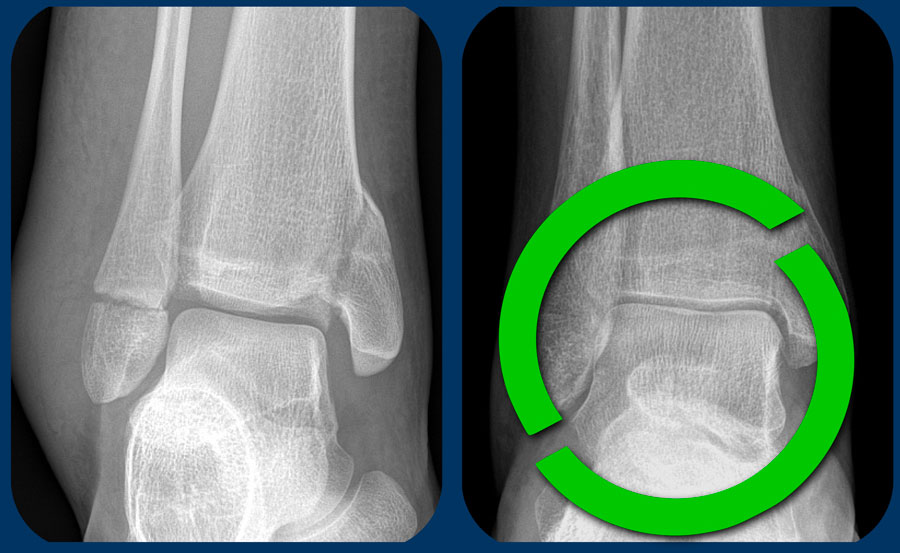

Gãy xương Tillaux

Cơ chế chấn thương gây ra gãy xương Weber B có thể dừng lại ở bất kỳ giai đoạn nào. Thường gặp nhất là giai đoạn 2 với đường gãy chéo của xương mác, nhưng đôi khi tổn thương chỉ dừng lại ở giai đoạn 1.

Thông thường đây là tình trạng đứt dây chằng chày mác trước và không thấy bất thường trên phim X-quang, tuy nhiên bệnh nhân sẽ đau nhiều tại vị trí đặc hiệu ở phía trước ngoài. Lực căng tại dây chằng chày mác trước đôi khi có thể gây bong điểm bám của dây chằng này tại xương chày, được gọi là gãy xương Tillaux. Bong điểm bám tại xương mác còn hiếm gặp hơn.

Hình ảnh

Trên tư thế chụp thẳng (AP) và tái tạo CT mặt phẳng coronal, chúng ta thấy gãy xương Tillaux ở giai đoạn 1. Không ghi nhận tổn thương gãy xương nào khác.

Hãy phân tích các hình ảnh này. Bạn có thể cần nhấp vào để xem ở kích thước lớn hơn.

Câu hỏi đầu tiên: Đây là gãy xương Weber A, B hay có thể là Weber C? Sau đó hãy cố gắng xác định giai đoạn và đánh giá xem cổ chân ổn định hay không ổn định.

Bạn có thể xem các hình ảnh tiếp theo để đọc phần thảo luận về các hình ảnh này.

Cuộn qua các hình ảnh.

Đây là gãy xương Weber B giai đoạn 4, thuộc loại không ổn định.